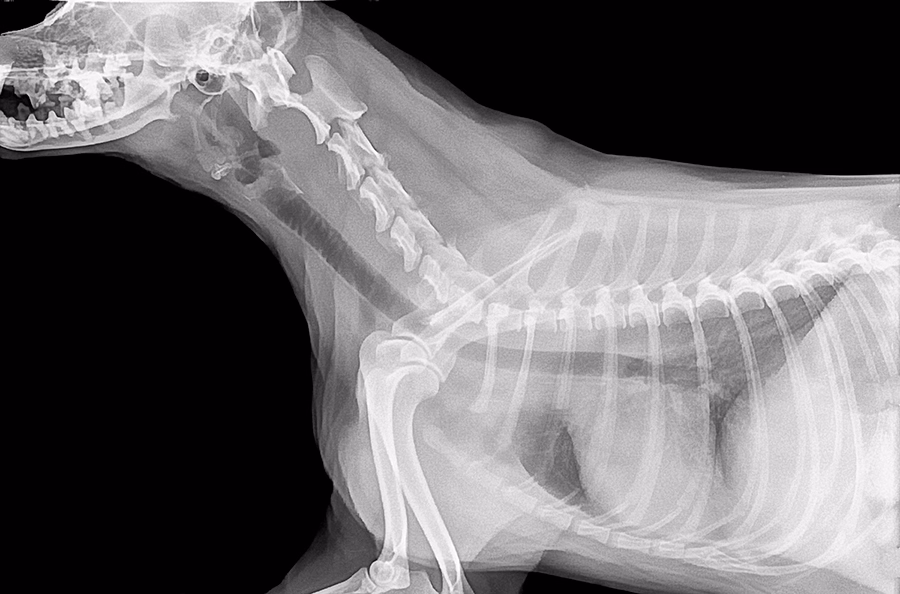

A continuación, en referencia a las pruebas complementarias, la radiografía convencional será de gran ayuda en el diagnóstico de la osteoporosis. Necesitaremos varias proyecciones de la zona afectada o que pensamos que puede sufrir osteoporosis.

En la radiografía el veterinario podrá observar varios signos que muestren la presencia de la osteoporosis en nuestra mascota. Se podrá ver en ocasiones adelgazamiento de la zona cortical (capa más externa del hueso), débil mineralización del hueso, así como osteólisis (zonas con menos densidad ósea) y presencia de fracturas patológicas en caso de haberlas. Esto se observará mejor en los huesos cúbito y radio.